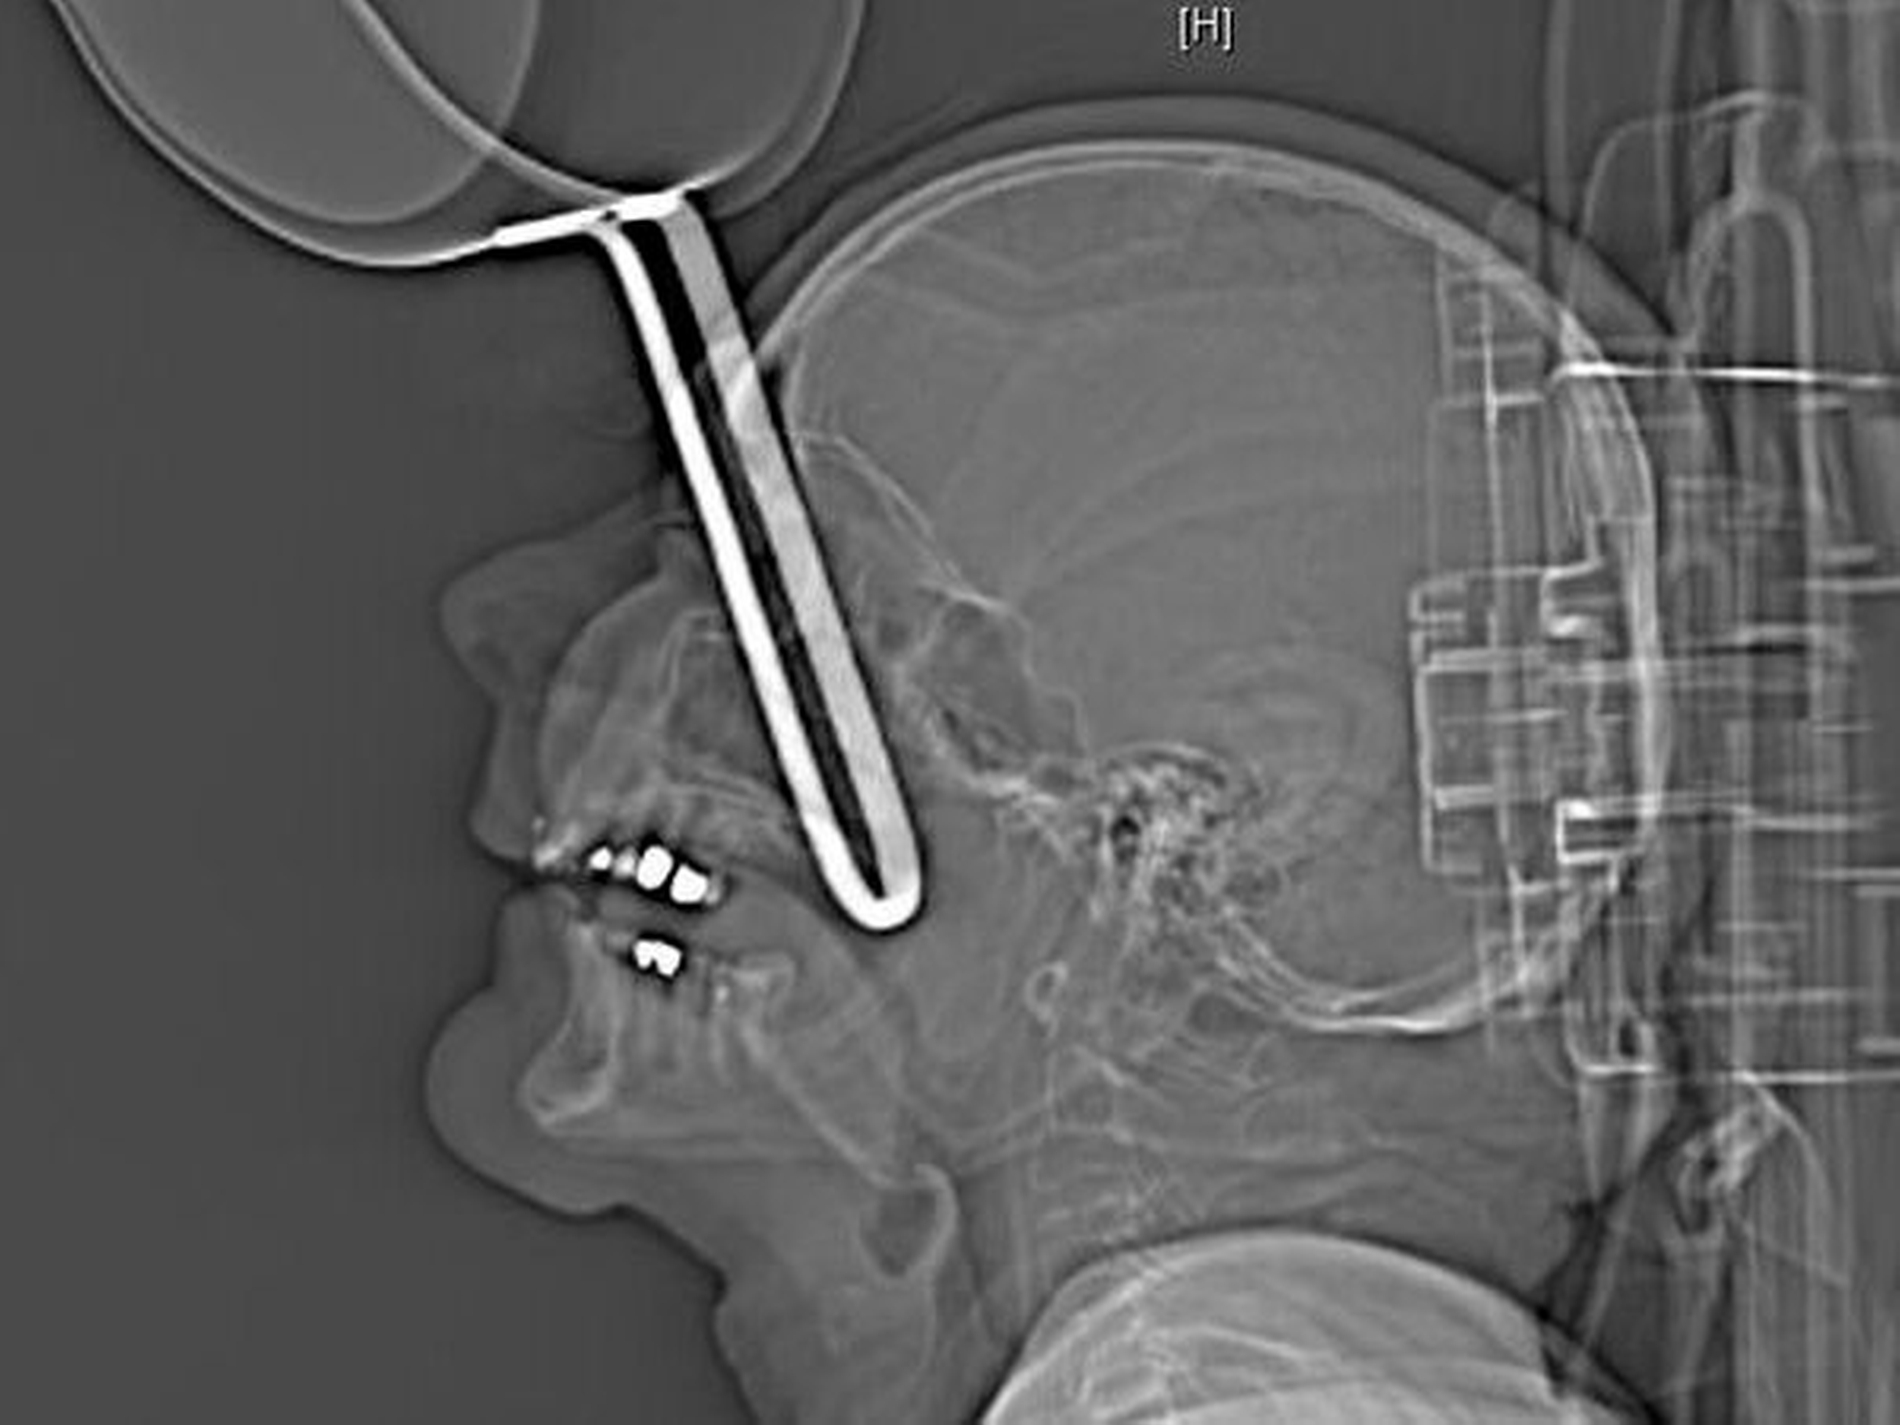

Im Rahmen der radiologischen Diagnostik wurden computertomografische Untersuchungen des Schädels, des Craniums und der Halswirbelregion durchgeführt. Hier zeigte sich der Kochtopfstiel 10 cm in situ steckend von oben kommend den rechten Orbitarand durchbrechend. Der Fremdkörper steckte mit dem Stiel voraus im rechten Mittelgesicht. Es zeigte sich nach intraoral keine Perforation.

Klinisch war das Ende des Stiels am Tuber maxillae rechts tastbar. Das Oberlid war mit dem Stiel am Infraorbitalrand eingeklemmt, so dass sich das Auge primär nicht öffnen und untersuchen ließ. Daraus stellte sich die Falldiagnose einer Perforation der Kieferhöhle und Orbita rechts mit Beteiligung des weichen Gaumens ohne intrakranielle Beteiligung.